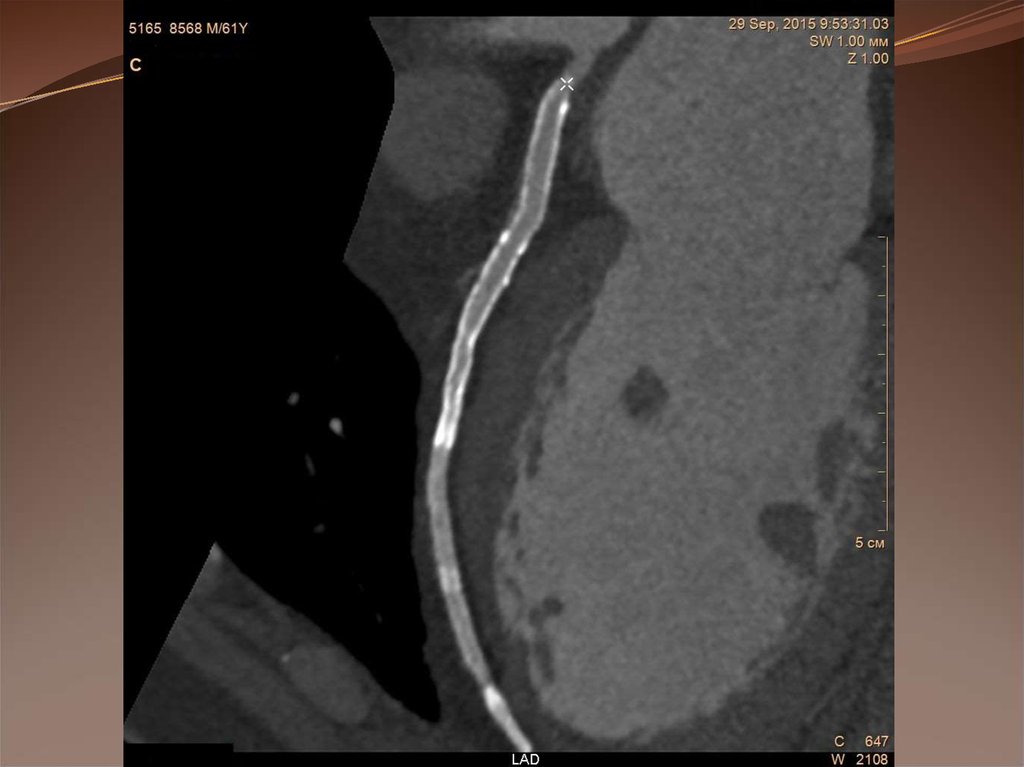

Рестеноз после стентирования ПМЖВ